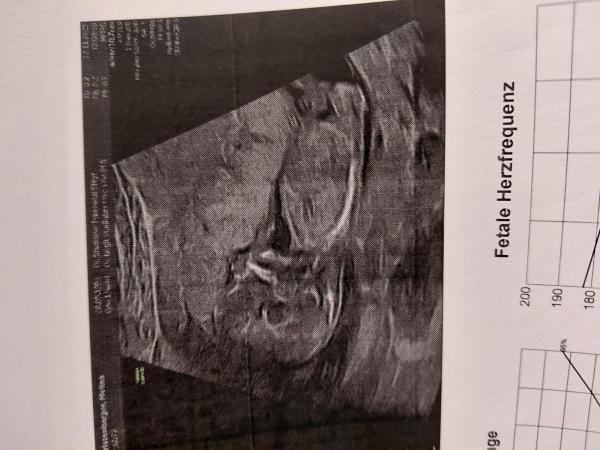

Hallo,  Junge oder Mädchen laut nub theorie ? Was sagt ihr ? :)

Bild zu Nub theorie - Schwanger - wer noch? Rund um die Schwangerschaft

Lt. Bild 2 finde ich definitiv Mädchen